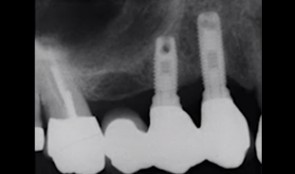

Prof. Bjarni PjeturssonIn this module, Prof. Bjarni Pjetursson will provide you an insight into the technical complications that you will encounter at implant-supported reconstructions. He will lecture about complications such as fractures of the veneering ceramic or framework, abutment and screw loosenings and fractures, and implant fractures. -